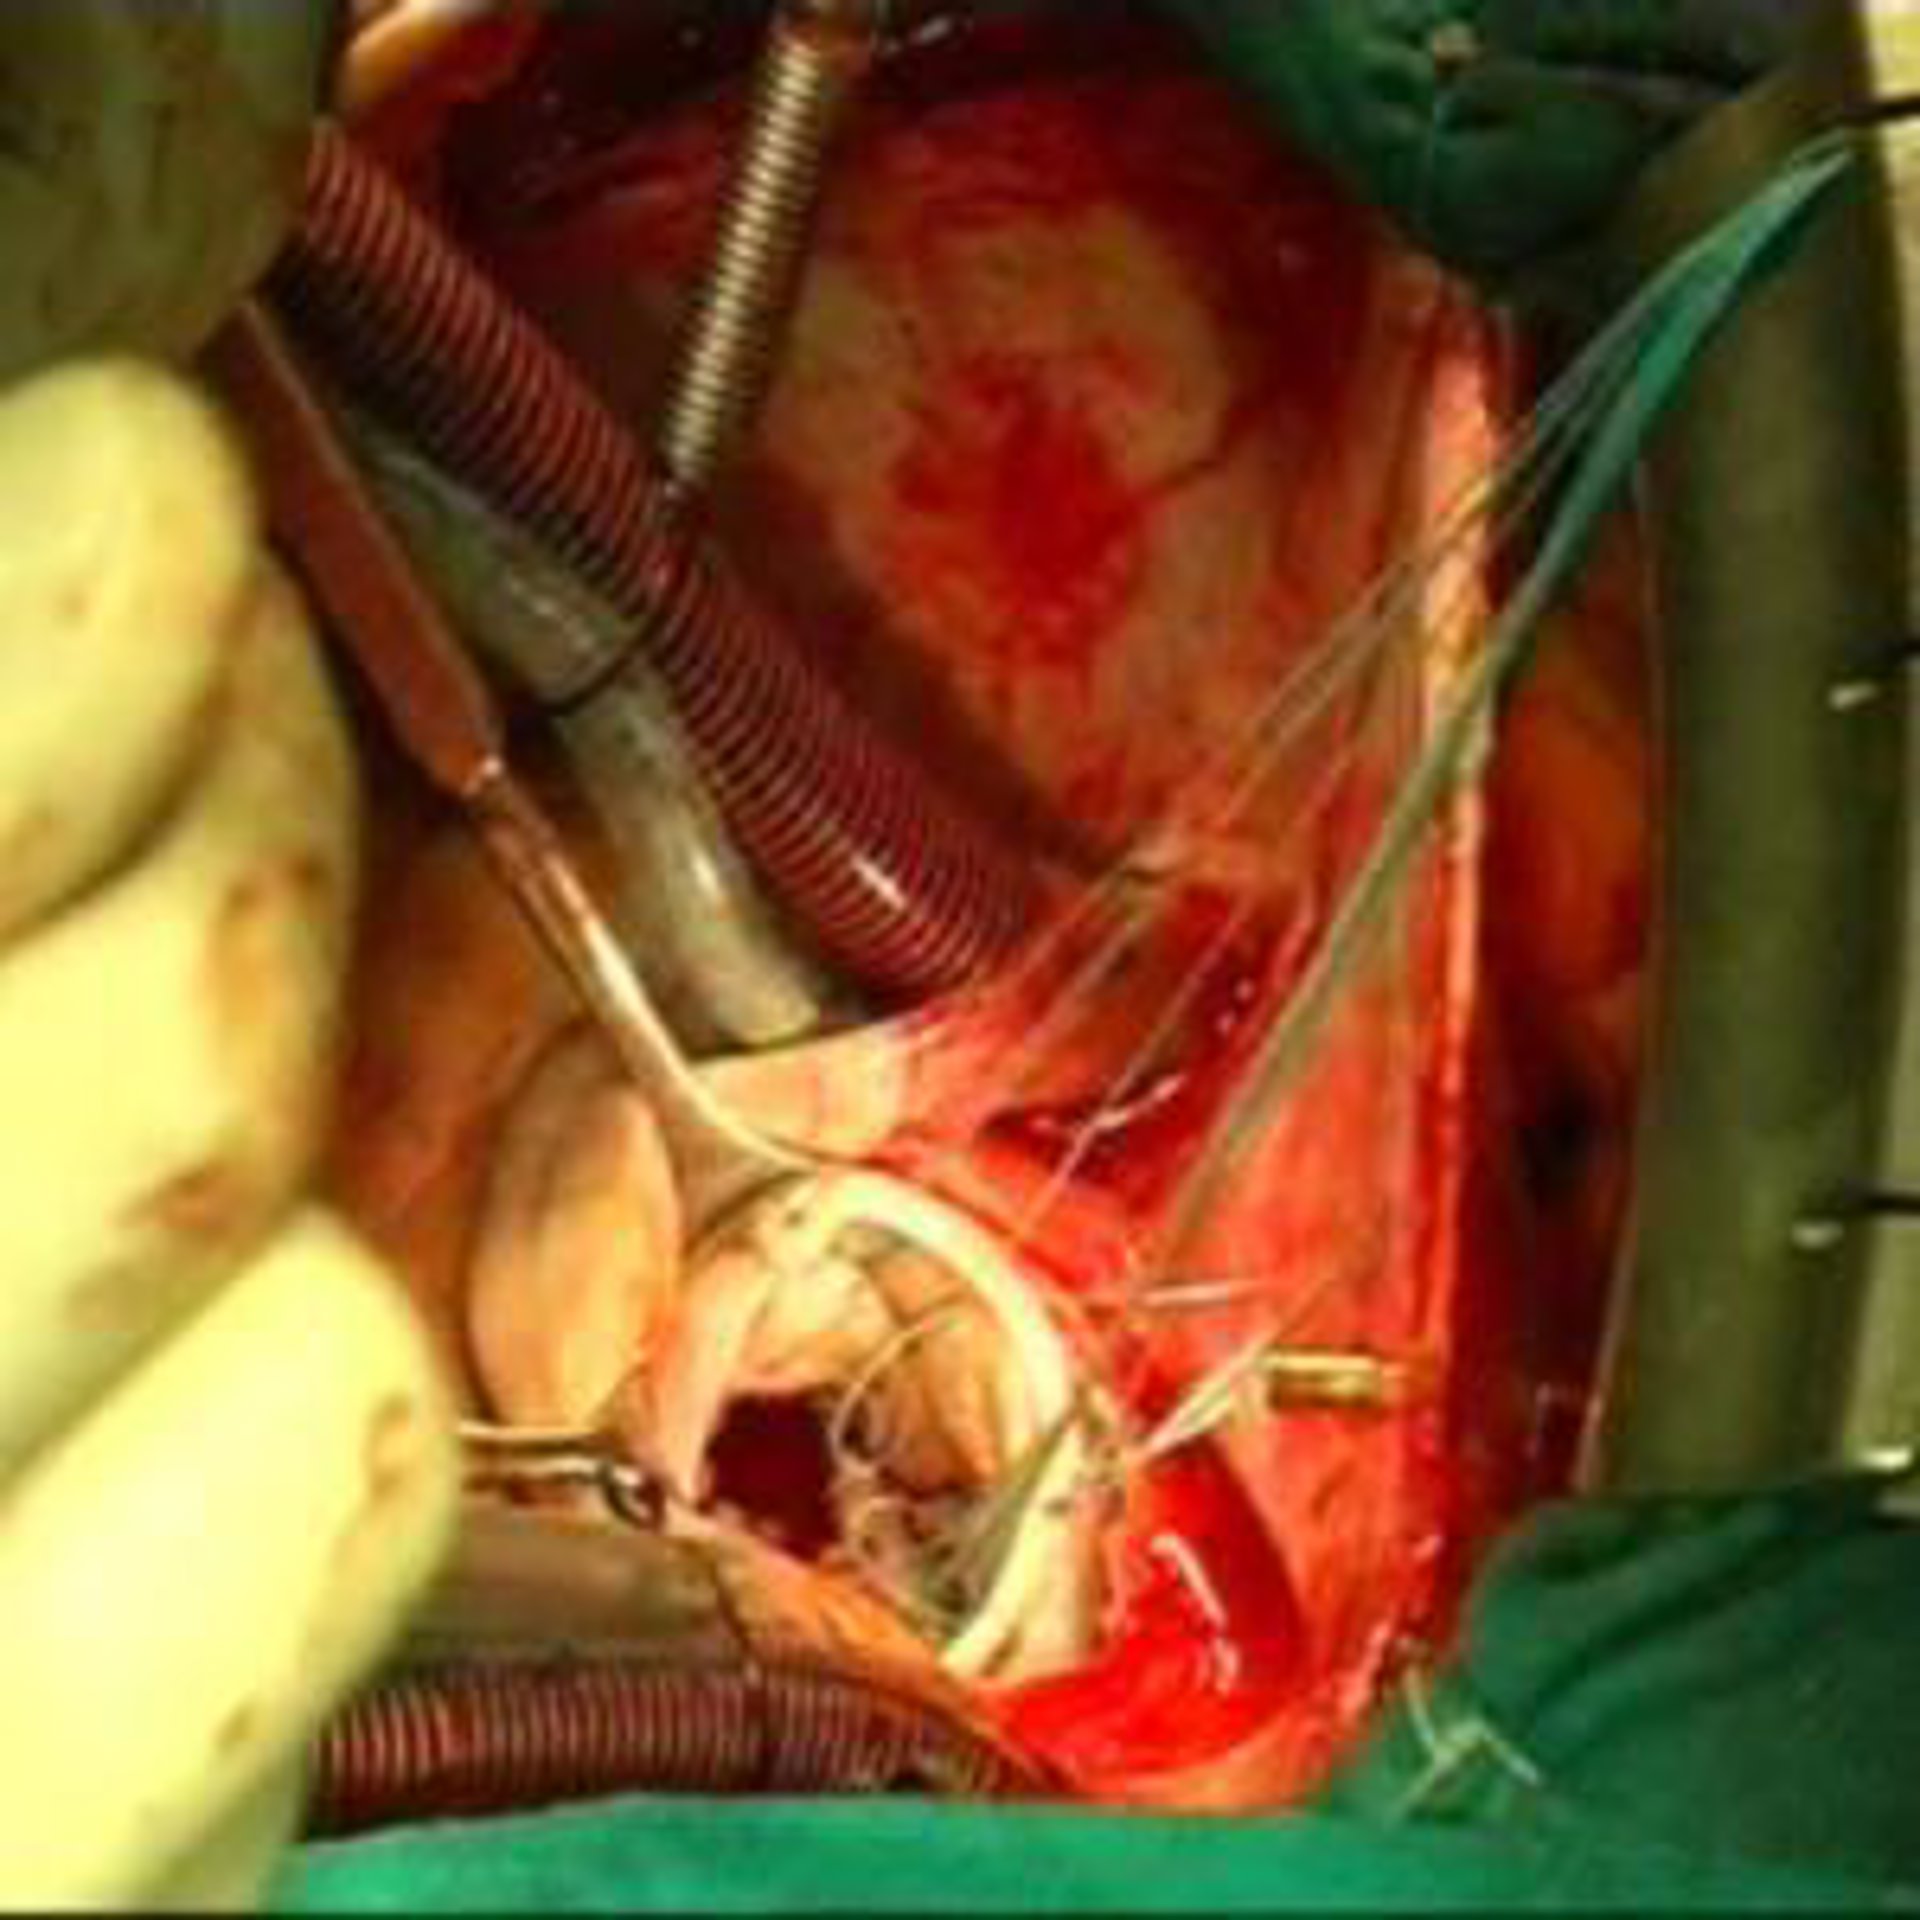

Al margen de estas medidas, uno de los grandes avances en las últimas dos décadas para la prevención de la muerte súbita cardiaca ha sido el llamado desfibrilador automático implantable, un pequeño dispositivo electrónico que se implanta en el pecho y que vigila continuamente el ritmo del corazón.

"En caso de que el corazón tenga un ritmo muy rápido, el dispositivo lleva a cabo un tratamiento eléctrico, ya sea estimulación eléctrica muy rápida o bien una descarga eléctrica, que en la inmensa mayoría de los casos corta la arritmia", afirmó Peinado.

Por otra parte, en caso de que el corazón vaya demasiado lento el desfibrilador automático actuará como marcapasos, lanzando impulsos eléctricos a una frecuencia cardiaca adecuada para el paciente.